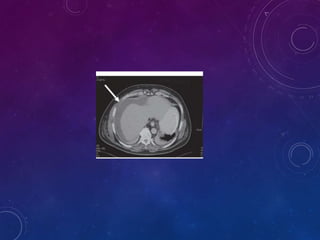

TOMOGRAFÍA COMPUTARIZADA

Con la CT se logra un alto grado de

resolución y detalle del parénquima,

de los vasos y de la relación del bazo

con estructuras vecinas.

La CT actual está más automatizada,

La CT se ha convertido en una

herramienta invaluable en la

valoración y tratamiento del paciente

con traumatismos cerrados,

TOMOGRAFÍA COMPUTARIZADA Con laCT se logra un alto grado de resolución y detalle del parénquima, de los vasos y de la relación del bazo con estructuras vecinas. La CT actual está más automatizada, La CT se ha convertido en una herramienta invaluable en la valoración y tratamiento del paciente con traumatismos cerrados,